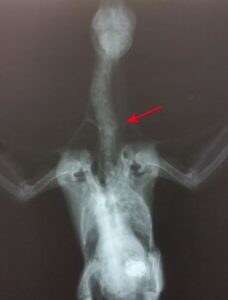

Soon after, an X-ray revealed that pigeon had suffered a broken neck, perhaps by crashing on her maiden flight, or at the hands of a cruel person who’d discovered her vulnerable on the ground.